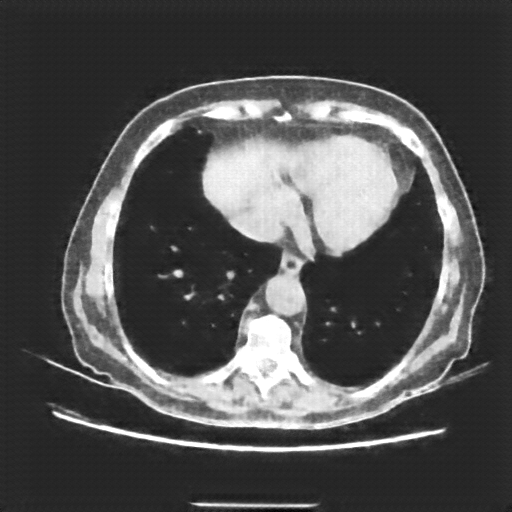

Original NATIVE CT scan (input)

Lung window (WL -600, WW 1500 β†’ Low βˆ’1350, High +150)

Reconstructed NATIVE CT scan (cycle consistency)